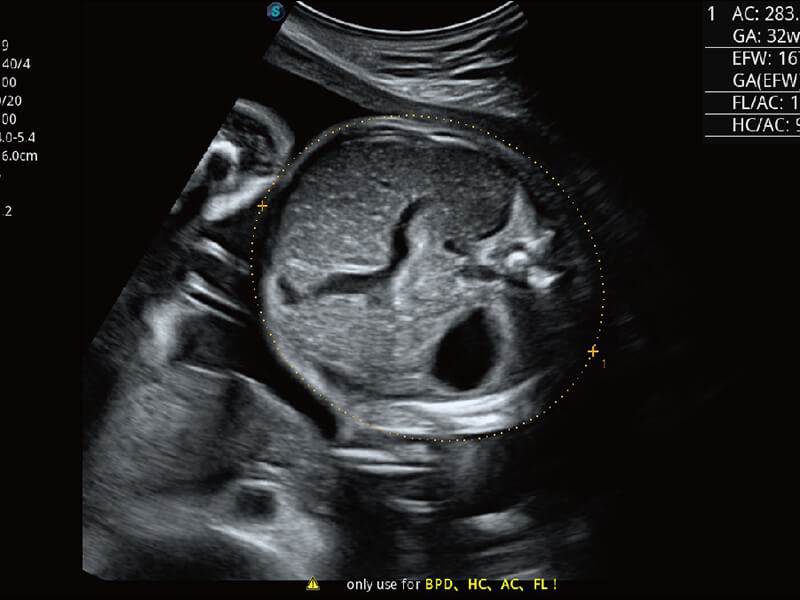

超宽频带技术,为容积成像带来优质的二维图像基础,为您呈现丰富的结构细节,栩栩如生地展示宝宝的宫内形态以及各种组织的立体结构。